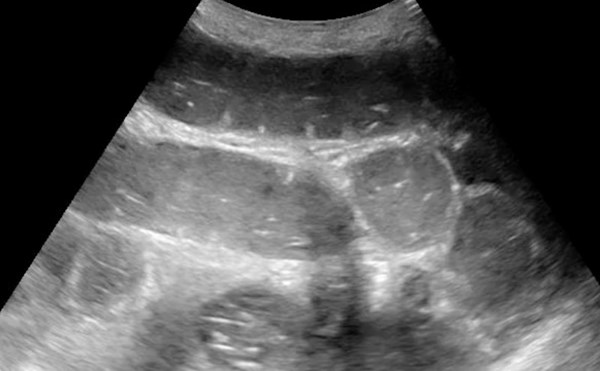

Advanced ultrasound can enhance the diagnosis of organ injury, viable tumor, and vascular pathologies at bedside.